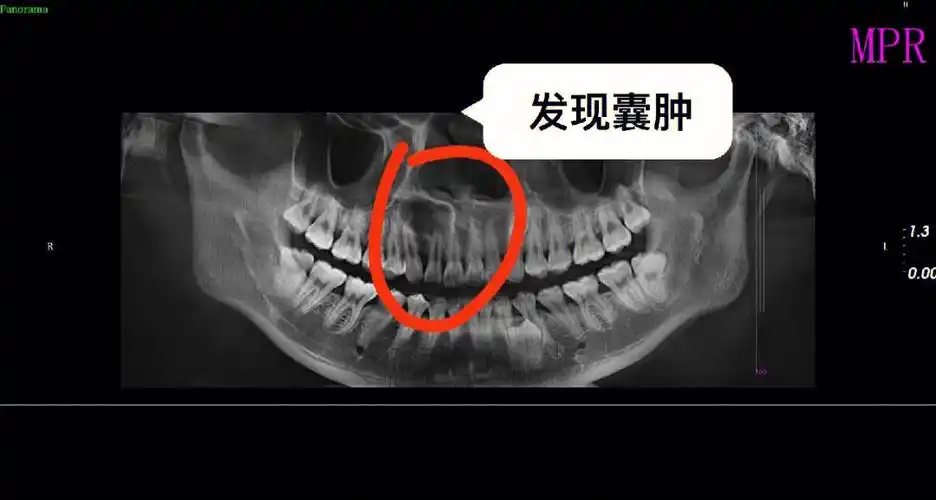

有根尖囊肿[二r]阶段二:回家直接做手术[三r]阶段三:一年后口腔检查